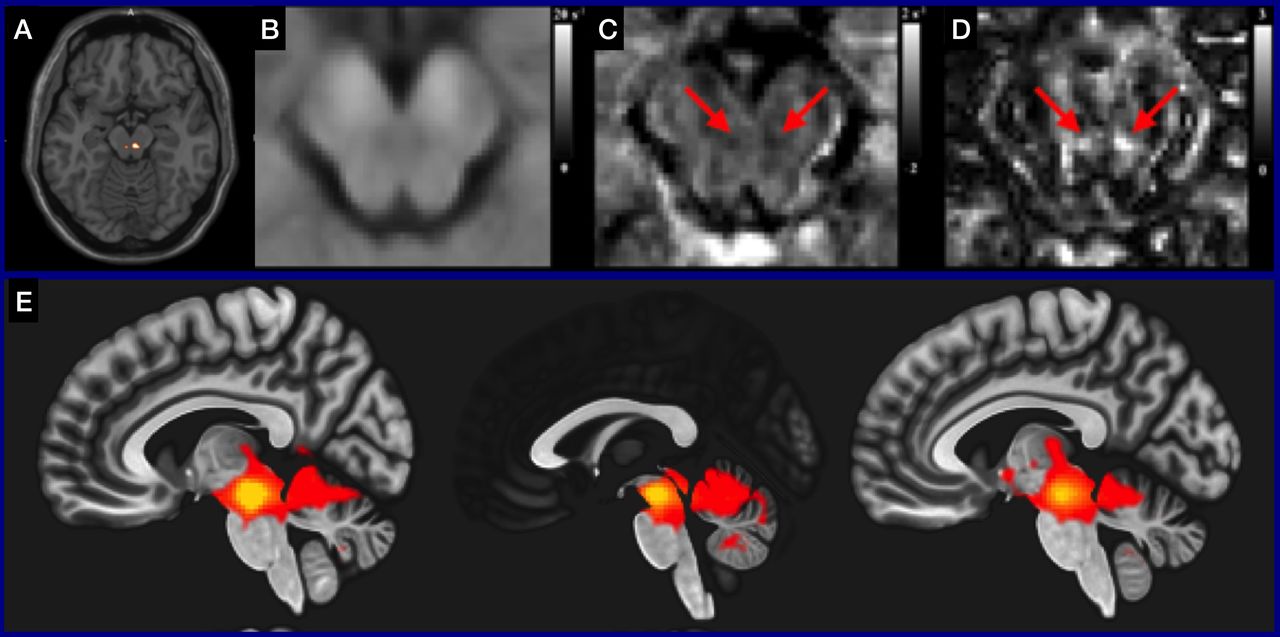

Effects of rTMS on alcohol use

Craving alcohol and an impaired ability to stop drinking despite adverse consequences are key features of alcohol addiction. This project aims to find a noninvasive brain stimulation method that can be used as treatment for addiction.